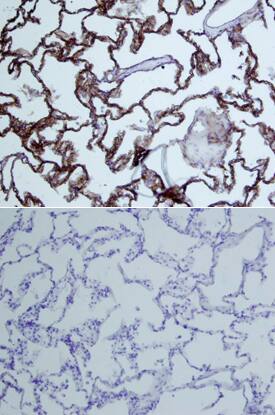

Dkk-3 antibody in Human Lung by Immunohistochemistry (IHC-P).

Dkk‑3 in Human Lung.

Dkk-3 was detected in immersion fixed paraffin-embedded sections of human lung array using Goat Anti-Human Dkk-3 Biotinylated Antigen Affinity-purified Polyclonal Antibody (Catalog # BAF1118) at 15 µg/mL overnight at 4 °C. Tissue was stained using the Anti-Goat HRP-DAB Cell & Tissue Staining Kit (brown; CTS008) and counterstained with hematoxylin (blue). Lower panel shows a lack of labeling if primary antibodies are omitted and tissue is stained only with secondary antibody followed by incubation with detection reagents. View our protocol for Chromogenic IHC Staining of Paraffin-embedded Tissue Sections.